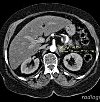

Магнитно-резонансная томография (МРТ) надпочечников. Исследование структуры надпочечников, основанное на регистрации ядерно-магнитного отклика (резонанса) ткани железы в ответ на индуцированное магнитное поле. МРТ надпочечников направлена на выявление масс желез, уточняя их местоположение, их структуру, их контуры, их корреляцию с окружающими тканями, что необходимо для планирования хирургического лечения. Использование контрастного усиления при МРТ надпочечников позволяет проводить морфологическую верификацию злокачественных новообразований (в том числе метастатических) и доброкачественных новообразований.

Оценка результатов